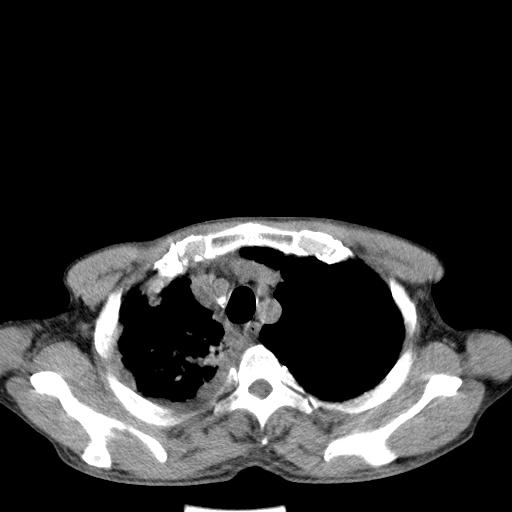

男性 75  咳嗽 一周前发热最高达39

右肺继发型tb并右侧tb性胸腔炎,右侧胸腔大量积液并右下肺膨胀不全,慢支肺气肿、多发肺大泡。建议抽胸水实验室检查并复查排除恶性在占位。

结核的基础上有纵隔淋巴结肿大,右侧有胸水,但右侧纵隔反而窄,说明有肺有不张。

再就是右下肺有块影,和不张混合,还是不能除外肺癌。

补充材料,患者2月份ct片大致正常,双侧胸腔积液,2月份抽胸水未发现ca细胞,现患者发热,痰多,各气管通畅,